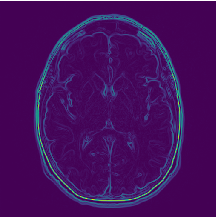

Training with the MRI dataset, which is made up of 150×\times150 gray-scale images, that is, each image is of shape (150,150,1) (Gray Scale = 1 channels). The sequential convolution feature extraction model is provided in Table 1 containing layer names, dimension, and parameters. Further, note that the CNN used in the experiment is also having the same architecture apart from the SVM classifier, which is replaced using a fully connected neural network. An example of the features extracted using a particular convolution layer on a particular slice is given as an example in Fig. 7. The generated feature vector will be used for the feature selection phase for reducing unnecessary features. LASSO regularization is used to select the optimal set of features and remove the features that may hamper the model performance. Convolutional feature extractor provides 2,49,536 features based on the total input data which has been significantly reduced to 5,240 features after LASSO feature selection is performed.

Refer to caption

Figure 7: Features extracted from a single slice in Block-1_Conv-1 layer.